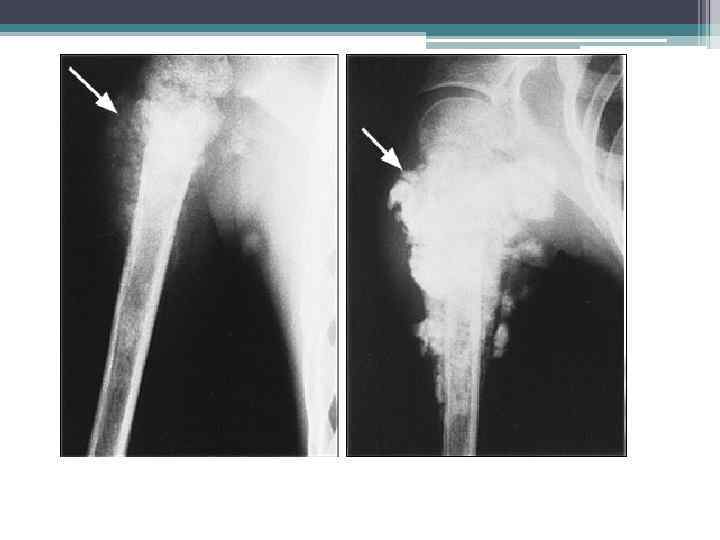

Опухоли злокачественные Остеогенная саркома: бедра (А), б/берцовой кости (Б), плеча (В)

Опухоли злокачественные Остеогенная саркома бедренных костей

Остеогенная саркома • Ценным рентгенологическим симптомом всякой остеогенной саркомы является омазаяноеть и неопределенность наружных контуров опухоли. Поэтому истинная форма опухоли и ее размеры лишь неточно мопут быть определены рентгенологически на основании некоторых вторичных признаков, как, , например, дугообразное оттеснение мягких тканей или увеличение расстояния между соседними костями, например, оттеснение надколенной чашки, расширение межкостного пространства голени, раздвигание пястных и плюсневых костей и т. д